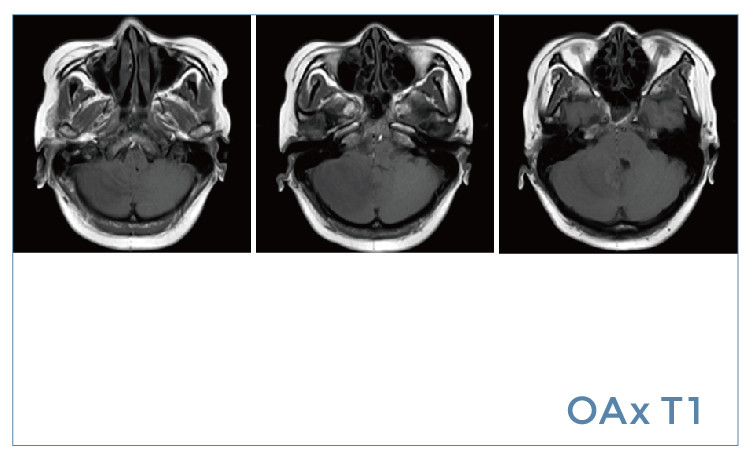

【朗润影像档案】磁共振影像病例分享(编号20190802)